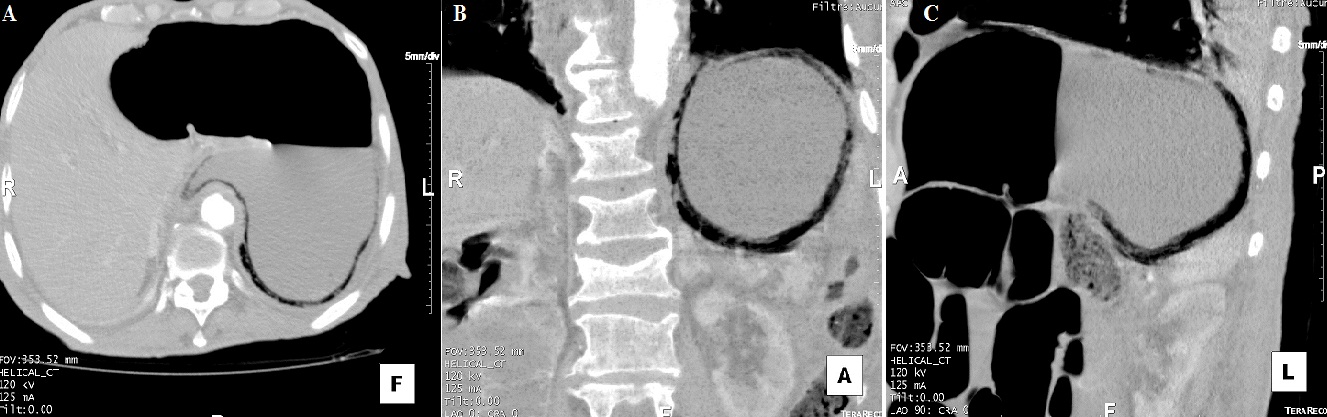

La gastrite emphysémateuse, caractérisée par la présence de gaz dans la paroi gastrique, est due à une infection par des germes "producteurs de gaz". Son pronostic est sombre avec une mortalité très élevée, imposant un diagnostic et un traitement précoces. Le tableau clinique n'est pas spécifique. Le diagnostic est souvent radiologique. La chirurgie est indiquée en urgence en cas de nécrose, de perforation, de péritonite ou de détérioration rapide de l'état du patient sous traitement médical. Nous rapportons le cas d'un homme de 79 ans, aux antécédents de maladie d'alzheimer depuis 3 ans, diabétique sous antidiabétiques oraux depuis 30 ans, qui s'est présenté aux urgences pour une douleur épigastrique évoluant depuis 48 heures. A l'examen, il présentait un état septique avec fièvre à 39,5º C et frissons avec tendance au collapsus. Il était polypnéique et il y avait une défense abdominale à l'étage sus-ombilical. Il existait une hyperleucocytose à 25 000/mm3, une CRP à 280 mg/l et une acidose métabolique. La tomodensitométrie abdominale (A,B,C) montrait du gaz dans la paroi gastrique et confirmait le diagnostic de gastrite emphysémateuse. Les axes vasculaires digestifs, en particulier le tronc coeliaque, étaient perméables. Il n'y avait pas d'aéoportie. Une antibiothérapie à large spectre couvrant les germes gram négatifs et les anaérobes a été démarrée, et une préparation du patient pour une chirurgie en urgence a été entamée mais le patient décédait d'une défaillance multiviscérale avec un syndrome de détresse respiratoire aigu, une heure après la réalisation du scanner abdominal.